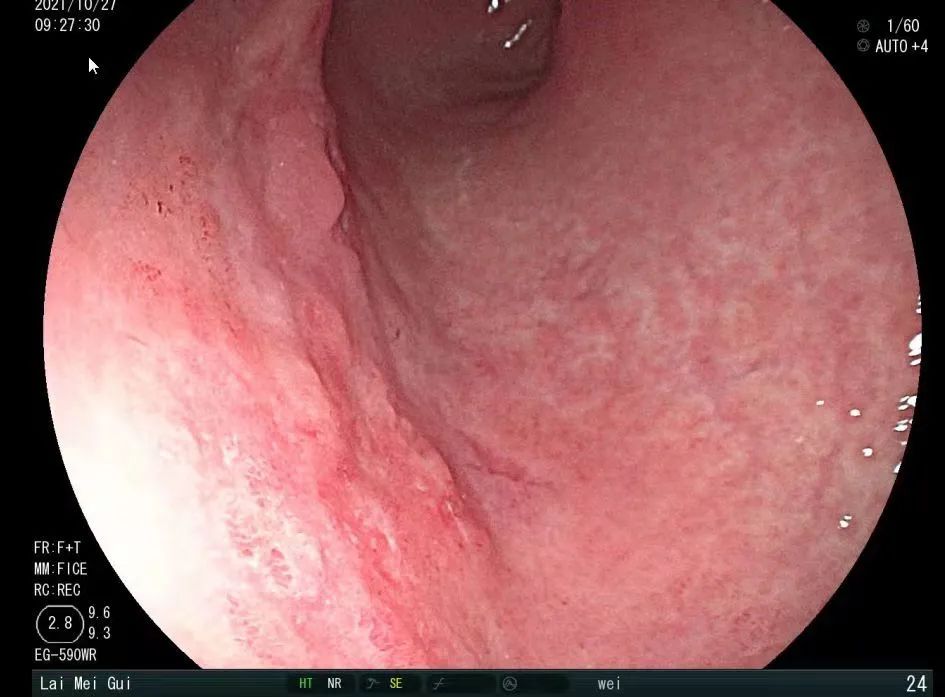

胃镜下患者的胃粘膜凹凸不平、粗糙,充气延展差,活检结果提示,林女士患有胃癌,而且是晚期。

胃镜下粘膜凹凸不平、粗糙,充气延展差